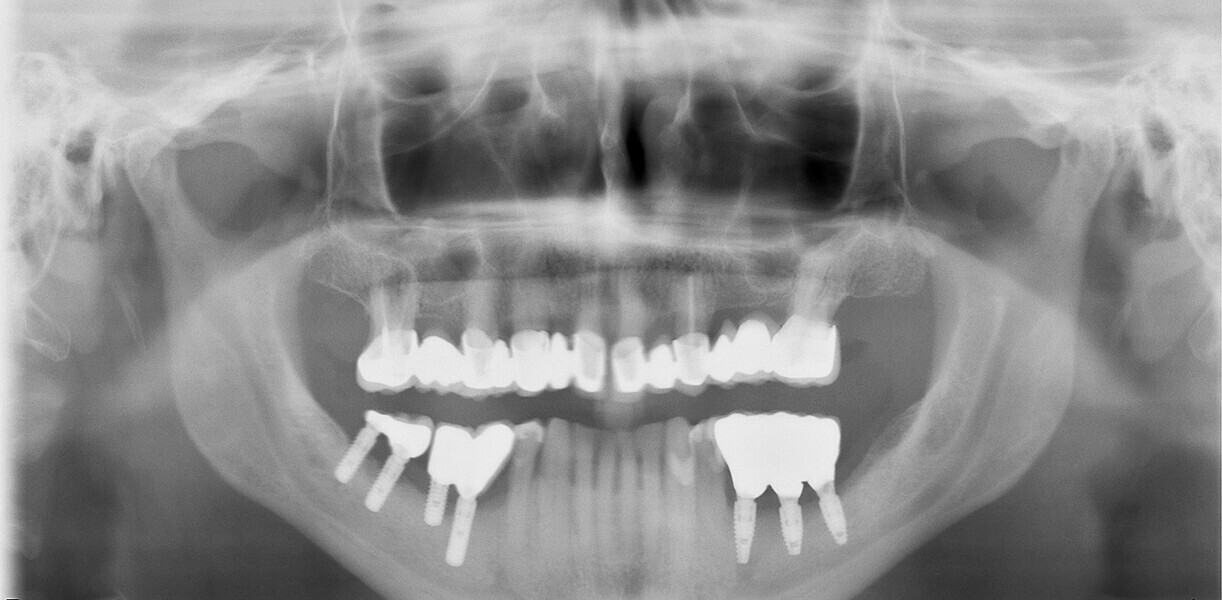

Fig. 13: Dental panoramic tomogram showing superstructure.